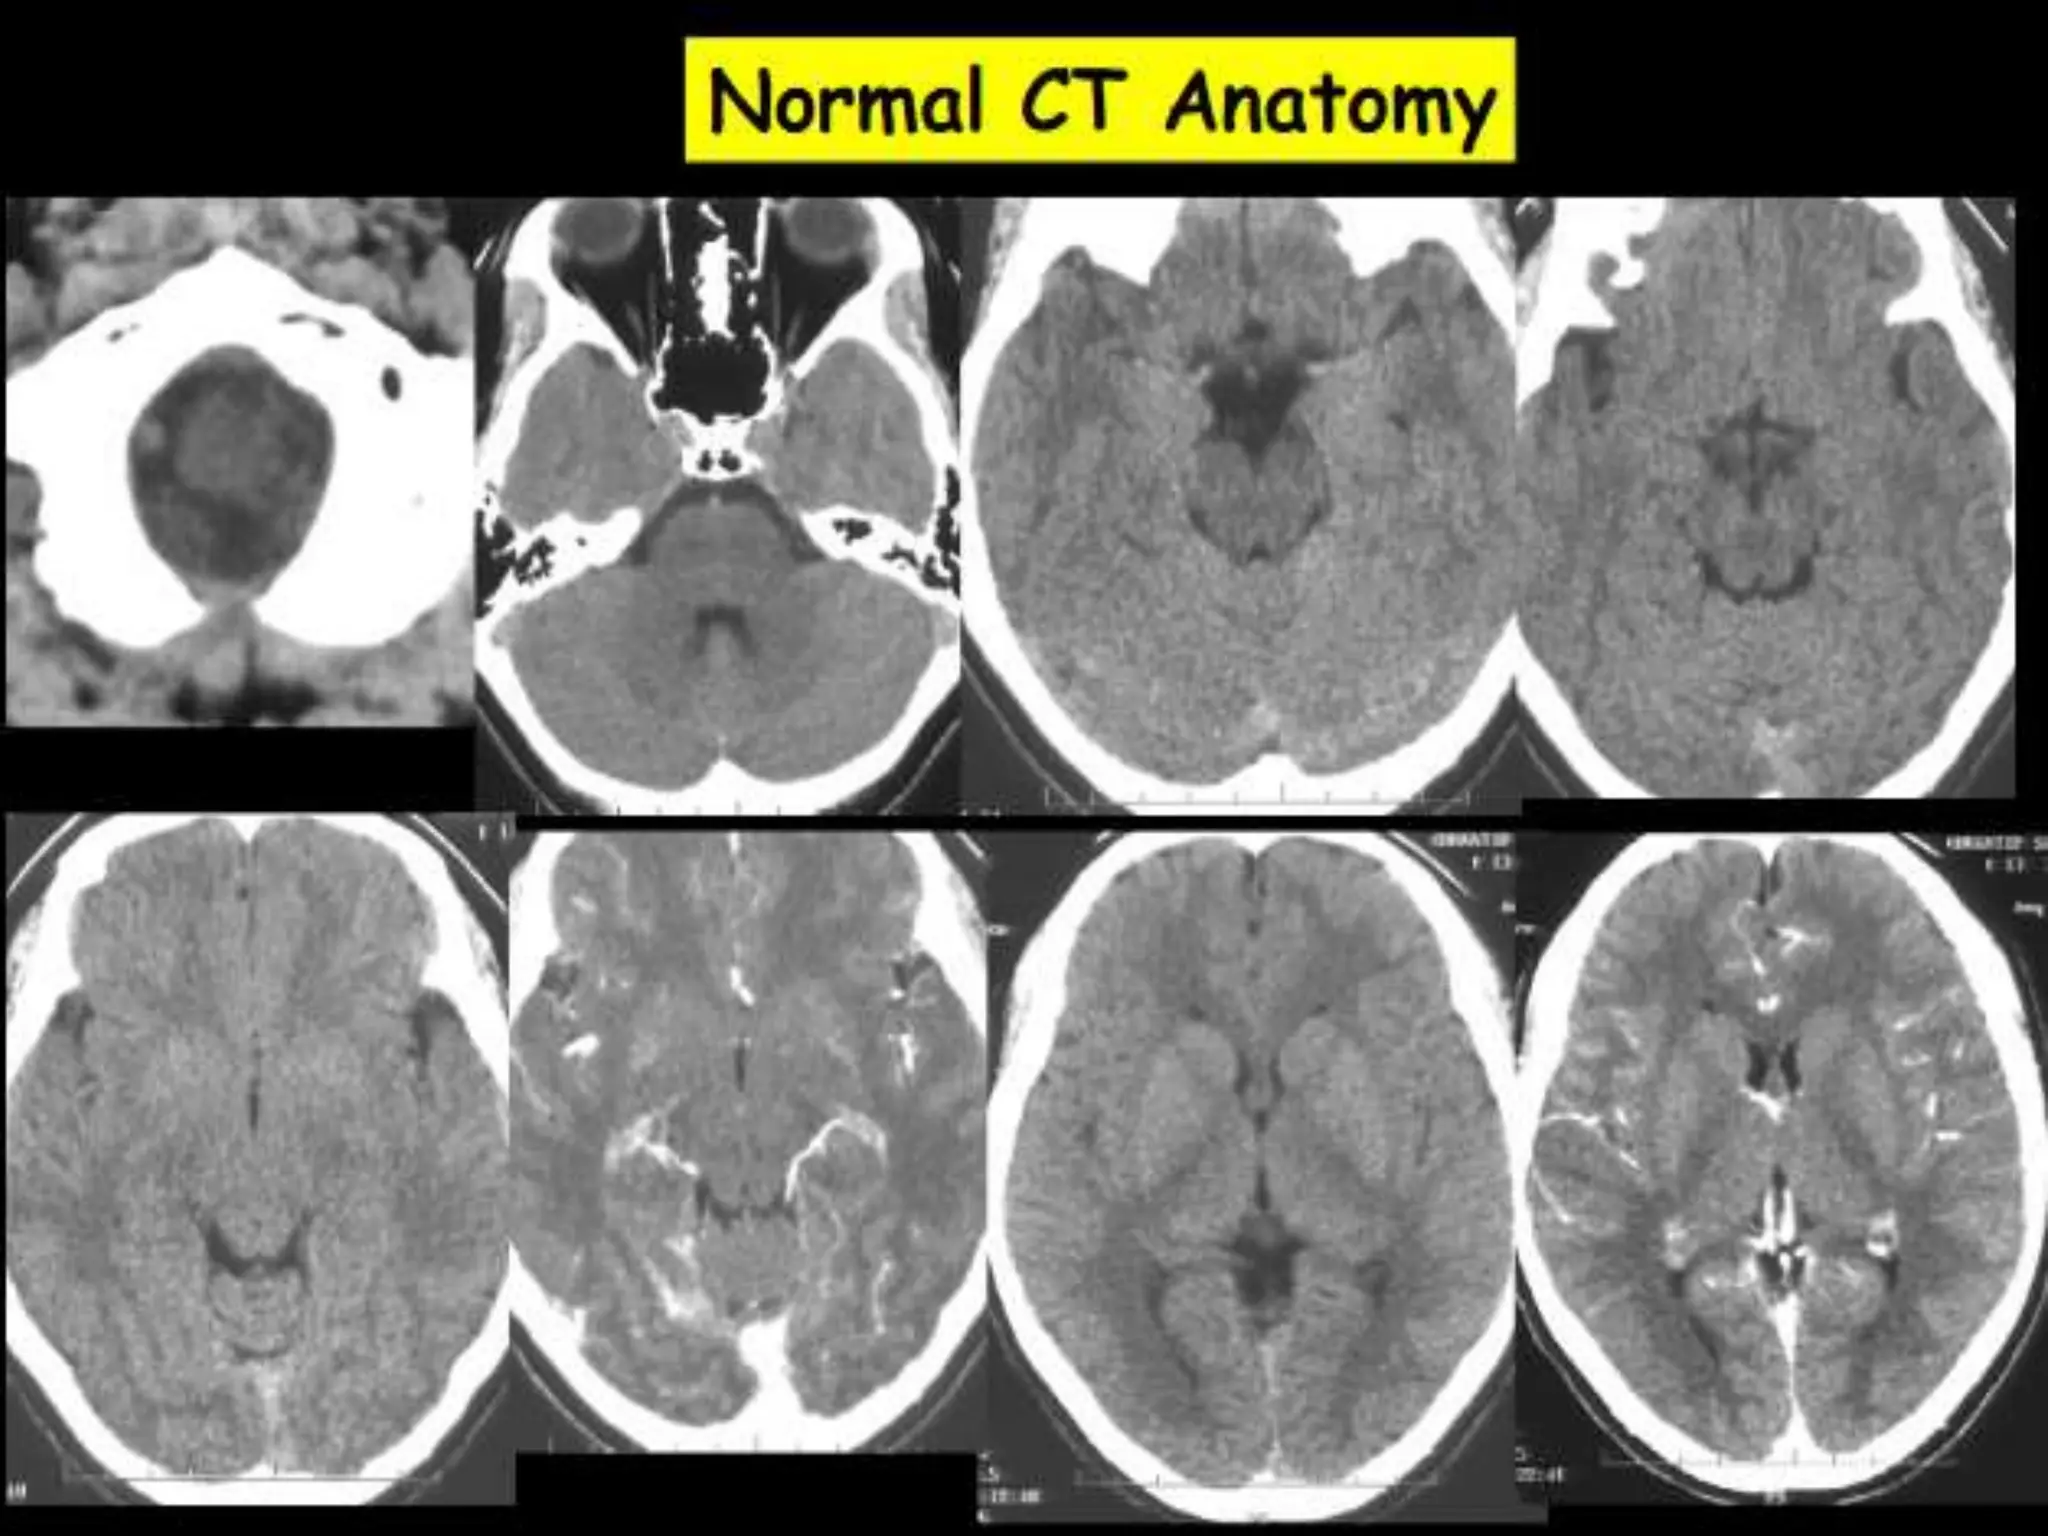

Axial CT Anatomy.

Sectional Anatomy: NormalAxial CT and MRI Anatomy. On CT and MR scans, the brain has been briefly viewed in infratentorial and supratentorial sections, as described below. CT scans are performed with a 15- to 20-degree angulation to the canthomeatal line at 8-mm increments. MRI scans are generally obtained parallel to the AC-PC line in the axial plane with 6-mm slice thickness. Using the sagittal view, the coronal sections are acquired parallel to the brain stem, and the sagittal sections are obtained perpendicular to the axial section. On MRI studies, cranial nerves IX and X can be demonstrated at this level because they emerge from the postolivary sulcus. The posterior aspect of the cerebellar hemispheres is outlined by the inferior portion of the cisterna magna.